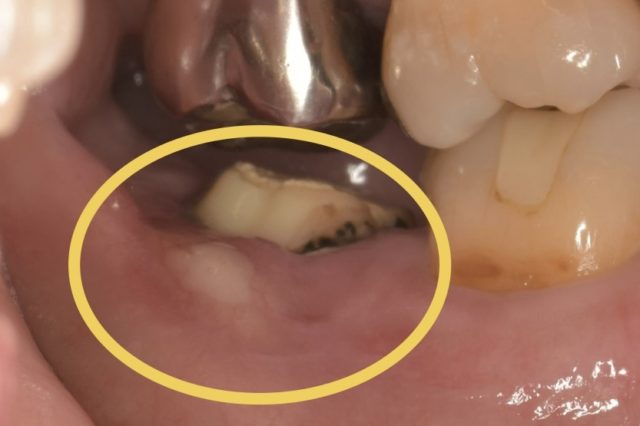

まずはパノラマ写真と口腔内写真をご覧下さい。

今回の部位は右下7番です。他院にて根管治療中ですが、痛みが治まらず当院を来院されました。なので仮蓋が詰められた状態です。

歯茎が白くなっている部分は膿の出口です。かなり大きいですね、、